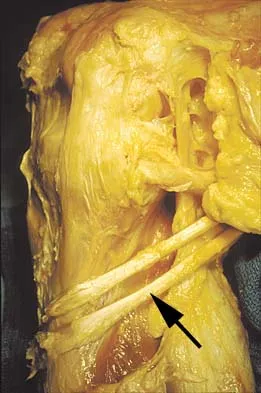

A patient who sustained a knife wound to the axilla 4 months ago now has profound interosseous wasting and generalized hand weakness. A brachial plexus injury is likely at which of the following locations in Figure 29?